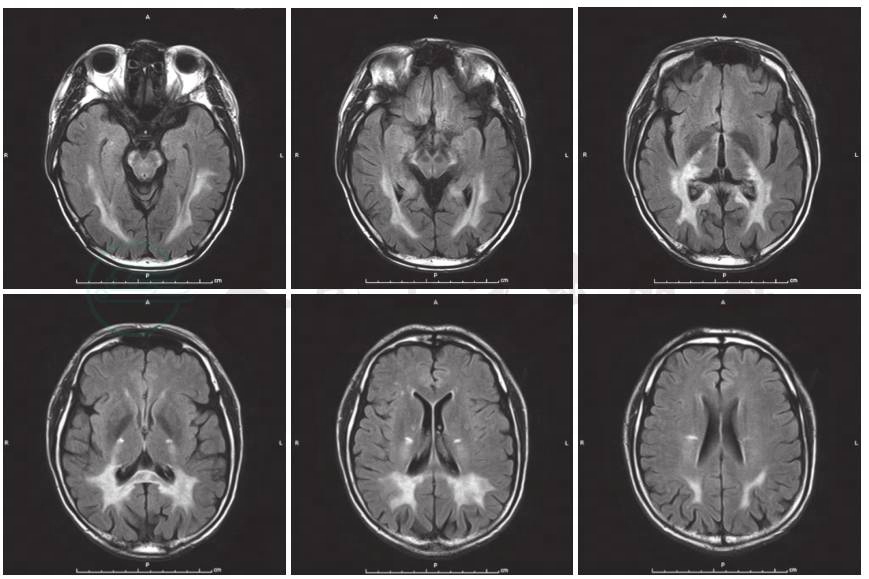

图1 患者头部MRI检查

FLAIR显示双侧顶枕颞叶、胼胝体压部及锥体束走行区对称性异常,呈FLAIR高信号

入院后完善认知功能评价,各项神经心理学量表评分为简易智能状态检查量表(MMSE)15分、蒙特利尔认知评价量表(MoCA)9分。实验室检查:血、尿、粪便常规,肝肾功能试验和血清电解质测值均于正常值范围;感染4项呈阴性反应,血清红细胞沉降率、超敏C反应蛋白正常;风湿免疫性疾病相关指标免疫球蛋白、补体正常,血清抗中性粒细胞胞质抗体谱PR3-ANCA 66RU/ml,其余各项均于正常值范围,抗可提取性核抗原(ENA)抗体谱和抗核抗体谱阴性。头部MRI提示双侧顶枕颞叶、胼胝体压部及锥体束走行区对称性异常信号,符合肾上腺脑白质营养不良表现(图1)。遂完善肾上腺脑白质营养不良相关检查:极长链脂肪酸C22 26.98mg/L、C24 44.53mg/L、C26 1.45mg/L、C24/C22 1.65、C26/C22 0.05。ABCD1基因检测显示ABCD1基因第1号外显子呈小片段缺失,TACCTTCGTCAACAGTGC 432-449 del导致145~150位氨基酸缺失(图2)。内分泌相关检查:血浆ACTH(8:00am)125.2pmol/L(参考值范围0~10.1pmol/L)、总皮质醇(8:00am)421.7nmol/L(参考值范围110.6~616.4nmol/L),24小时尿皮质醇123.9nmol/24h(参考值范围33.9~285.7nmol/24h),性腺轴激素硫酸脱氢表雄酮(DS)1.8μmol/L(参考值范围1.2~8.6μmol/L)、雌二醇(E2)12.5pmol/L(参考值范围73.0~175.8pmol/L)、睾酮(T)9.9nmol/L(参考值范围 13.4~23.6nmol/L)、FSH 5.6IU/L(参考值范围1.4~18.1IU/L)、LH 6.85IU/L(参考值范围1.5~9.3 IU/L)、孕酮(P)0.73nmol/L。临床考虑肾上腺脑白质营养不良。入院后未予特殊治疗。

X连锁型肾上腺脑白质营养不良具有特征性的头部MRI表现为脑白质对称性长T1、长T2信号,可累及胼胝体及脑干;病变由后向前发展逐一累及枕、顶、颞、额叶;增强后病灶周围区域强化,呈“蝴蝶”状。该例患者MRI可见头后部白质对称性长T1、长T2信号,支持诊断。